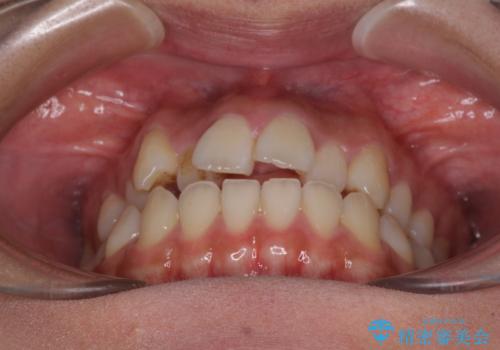

- 前歯の開咬と、上顎前歯の八重歯やデコボコを気にして来院された患者様です。

上顎歯列が狭窄していたため、急速拡大装置により上顎骨を側方に拡大し、その後ワイヤー装置にて矯正治療を行うこととしました。